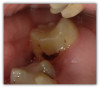

Figure 4a through Figure 4e show the technique using a bulk fill flow with a bulk fill capping layer. There was a carious lesion on tooth No. 19 requiring a deep excavation of decay close to the pulp and cotton roll isolation. Practitioner did an indirect pulp cap using a light curable bioactive syringeable flowable that can be used for direct and indirect pulp capping, and then applied a layer of the bulk fill flow, which offered a good glossy appearance without polishing. Kerr SimpliShade Bulk Fill Flow and Bulk Fill Packable were used. Although most bulk fill flows are transparent, this one successfully blocks the white opaque resin-modified calcium silicate filled liner (Bisco TheraCal LC). The practitioner used bulk fill packable (Kerr SimpliShade Bulk Fill) as the capping layer in a single increment. In the author's opinion, this single shade bulk fill system offers excellent esthetics and gives an outcome similar to layering. The patient reported no post operative sensitivity or discomfort after the restoration was performed.

Fig 4a. Carious lesion on tooth No. 19 requiring

a deep excavation in which an indirect pulp cap was performed using a light curable resin-modified calcium silicate (Bisco TheraCal LC), and

the tooth was subsequently restored in two separate steps using Kerr SimpliShade Bulk Fill Flow followed by SimpliShade Bulk Fill Packable

as the capping layer.

Fig 4a.

Fig 4b. Carious lesion on tooth No. 19 requiring

Fig 4b.